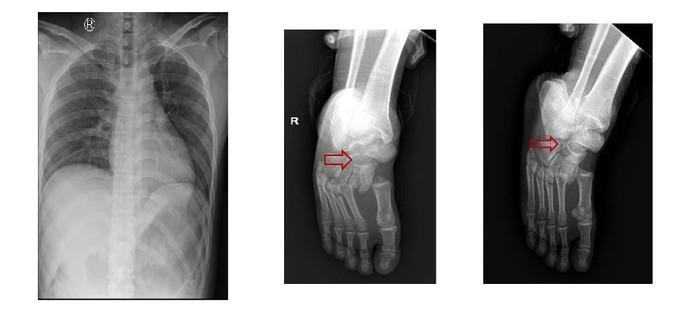

Kết quả chụp Xquang ngực thẳng, cổ bàn chân phải của các bệnh nhân. (Ảnh: Bệnh viện cung cấp)

2 bệnh nhân nam nhập viện trong tình trạng đau đớn, liệt hoàn toàn 2 chân, bí tiểu… Theo bệnh sử, trong lúc nam bệnh nhân 28 tuổi (quê ở Hải Dương) đang sửa cáp thang máy thì người đồng nghiệp (26 tuổi, quê Tiền Giang) bước vào thang khiến thang quá tải rơi xuống từ lầu 7.